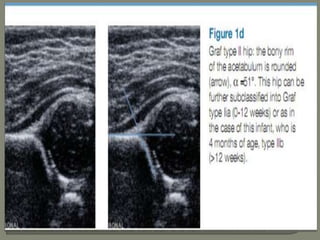

Graf α Angle

The Graf α angle is measured in the coronal plane

Defined as the angle formed between the vertical cortex of the

ilium and the acetabular roof.

Graf β Angle

The Graf β angle is formed by a line through the vertical

ilium and the cartilaginous acetabular labrum Graf β angle

greater than 55° is abnormal.

With superolateral femoral head displacement, the labrum

is elevated, thereby increasing the β angle